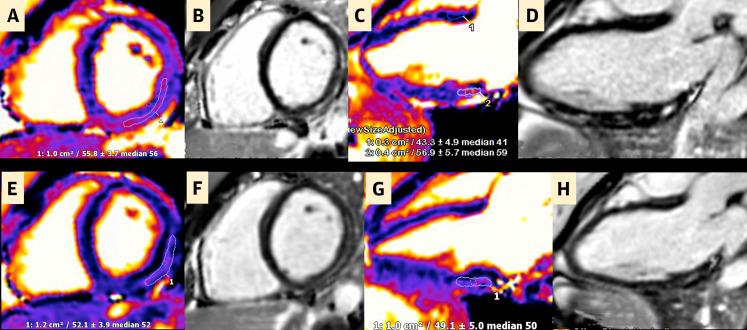

Cardiac Magnetic Resonance Imaging Midterm Follow Up of COVID-19 Vaccine-Associated Myocarditis.

JACC Cardiovasc Imaging. 2022 Oct;15(10):1821-1824. doi: 10.1016/j.jcmg.2022.01.008. Epub 2022 Mar 16.